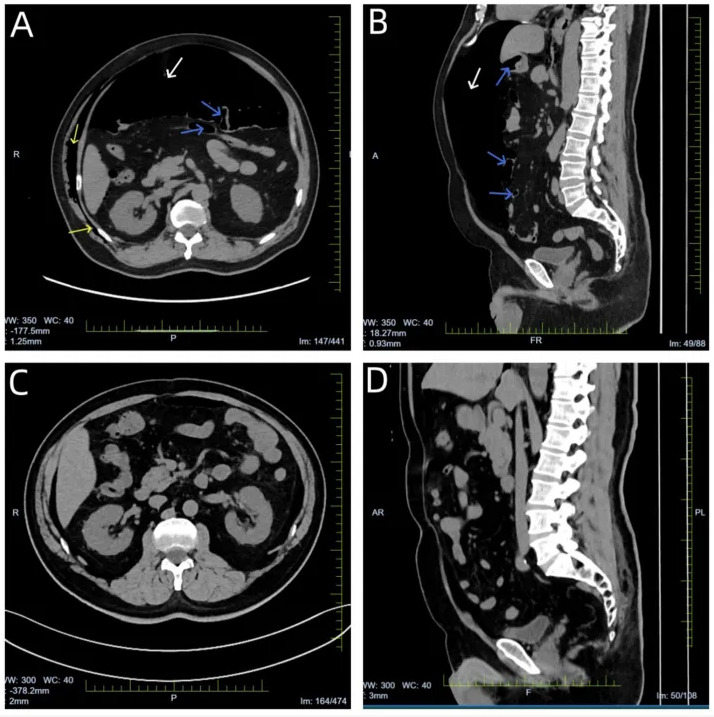

30分钟后,注射器内气泡量明显减少,患者诉腹部胀气显著缓解。行急诊胸腹部CT检查:纵隔少量积气,右侧胸腹壁及肌间隙多发积气,腹腔内仍残留大量游离气体,空肠少量积气伴管腔轻度扩张:下图A、B)。

后续治疗(其中留置胃管2天、禁食3天及支持治疗),复查腹部CT,显示气腹已基本消失(下图C、D)。经过两周抗生素治疗,肺部感染好转出院。